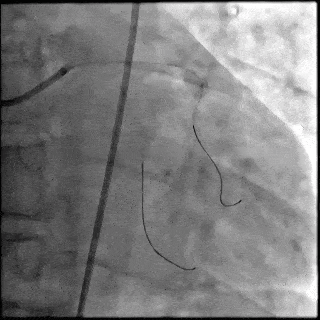

【DSA图 左冠治疗前造影】

【DSA图 前降支支架释放】

【DSA图 回旋支导丝顺利通过病变】

【DSA图 治疗结束造影】

5月28日8:00,葛均波院士团队在中山医院16号楼16楼中伟厅成功连线喀什二院导管室,沪喀远程手术正式开始。8:35,新疆喀什二院导管室内股动脉入路通路建立后,行左右冠脉造影示左前降支中段存在85%的严重狭窄,狭窄位于血管分叉路口且紧邻心肌桥;且左回旋支中段近乎闭塞,血管细窄且迂曲,病变弥漫。8:59,葛院士于上海操控血管介入机器人主端PANVIS COF,将指引导管送至左冠脉开口,并操控主支导丝和分支血管保护导丝通过狭窄病变,后送至前降支和对角支血管远端以建立轨道,同时利用介入机器人的微速调整功能避开心肌桥,以亚毫米级精准定位释放1枚支架。在成功处理患者左前降支病变后,葛院士通过搓捻机械操纵杆,远程精细调整导丝“进攻”方向,顺利通过左回旋支次全闭塞病变。因血管相对细小且病变弥漫,葛院士决定采用单纯球囊扩张术处理,即刻造影提示几乎无残余狭窄,避免了额外的支架植入。10:10,撤出所有导丝及导管,手术顺利结束。